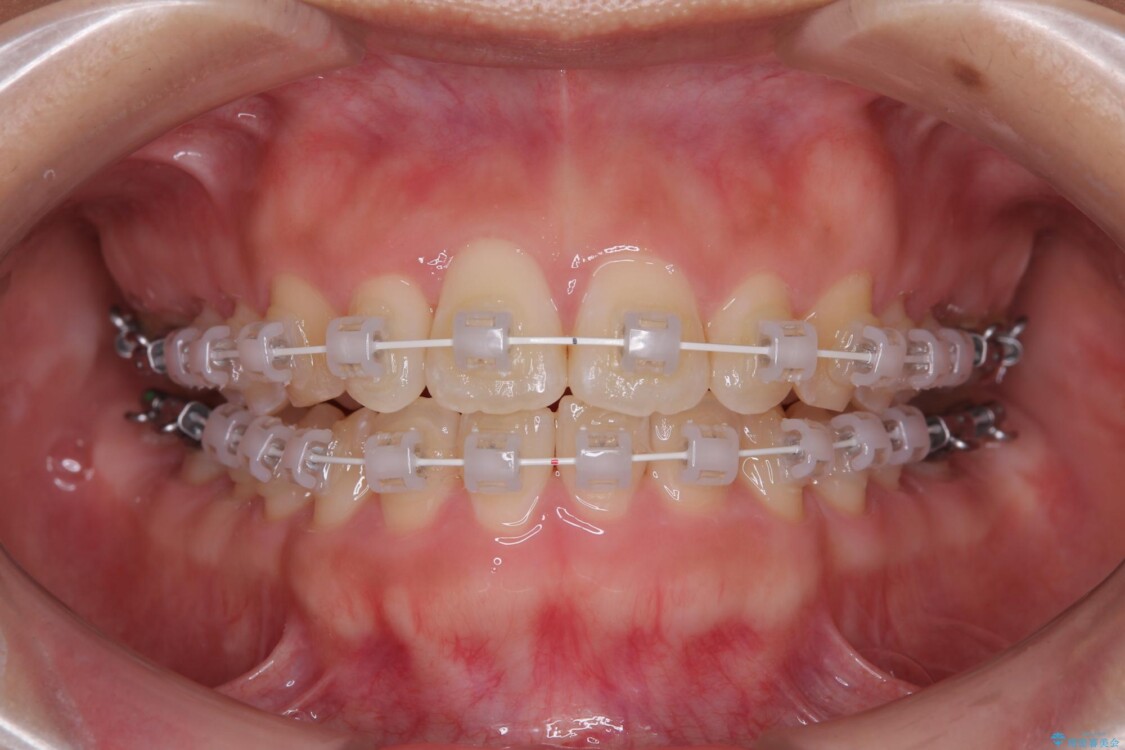

治療終了時

前歯が自然なアーチにきれいに並び、正中(上下の中心線)も整い、咬み合わせも良好です。

側方拡大することで、非抜歯であるにも関わらず前歯が前方に出ることなく、バランスの良い仕上がりとなりました。

治療後

• 目立ちにくい表側装置で1年完了!狭いアーチを側方拡大し前歯のデコボコを整えた症例 治療後画像